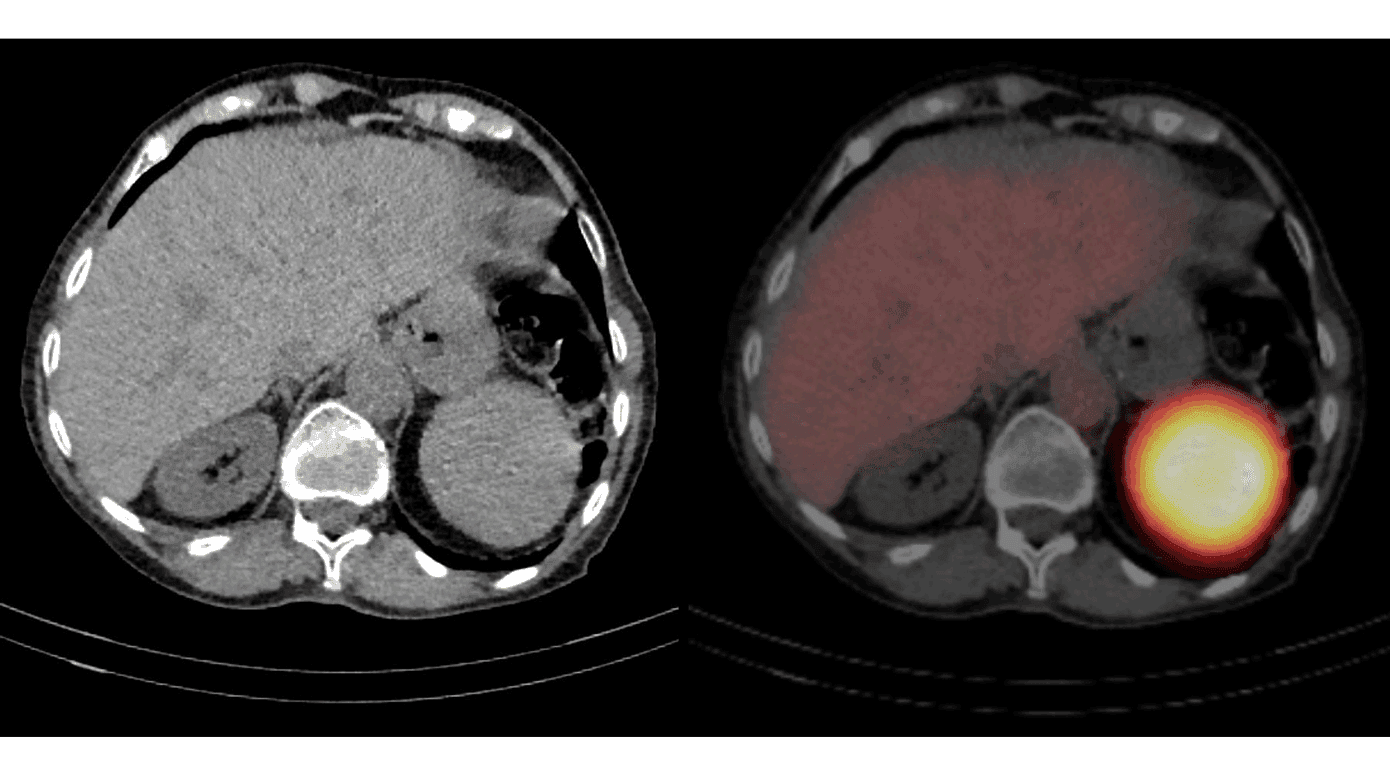

En 80-årig kvinde, splenektomeret i 1984 på grund af kronisk anæmi sekundært til hereditær sfærocytose, blev henvist til udredning for mindre, utilsigtet vægttab. CT af thorax og abdomen viste en velafgrænset, homogen proces under venstre diaphragmakuppel. Mistanken om miltvæv blev bekræftet ved hjælp af miltscintigrafi. Ved undersøgelsen fik patienten udtaget erytrocytter, som blev denatureret og mærket med 99mTc. Efter injektion af de radioaktivt mærkede og denaturerede erytrocytter blev der udført single-photon emission CT (SPECT) kombineret med konventionel CT med henblik på anatomisk lokalisationsbestemmelse. Undersøgelsen viste kraftig aktivitet i en proces i miltlejet, hvilket repræsenterede akkumulation af denaturerede erytrocytter, foreneligt med miltvæv. På de viste billeder ses også lav, fysiologisk erytrocytaktivitet i leveren og aorta.

En eller flere bimilte findes hos ca. 15% af befolkningen. Efterladte bimilte i forbindelse med splenektomi kan efterfølgende undergå hypertrofi, dog sjældent beskrevet så udtalt som i dette tilfælde. Det beslægtede fænomen splenose kan ses ved heterotopisk autotransplantation af miltvæv i forbindelse med traume eller kirurgisk indgreb.